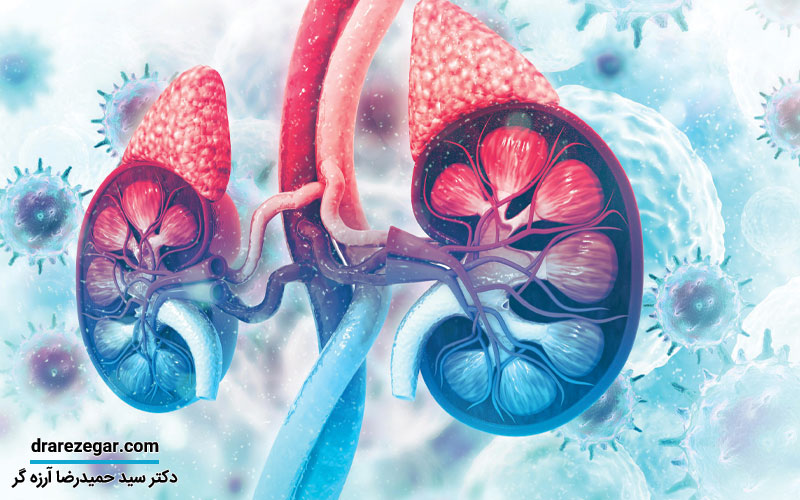

غدد فوق کلیوی یا غده های آدرنال به عنوان غدد درون ریز شناخته می شوند که می توانند در تنظیم مستقیم بدن یعنی ثابت نگه داشتن مواد موجود در محیط داخلی بدن و وضعیت کلی آن نقش مهمی داشته باشند. در این مقاله از سایت دکتر سید حمیدرضا آرزه گر قصد داریم در مورد غدد فوق کلیوی یا غده های آدرنال صحبت کنیم. اگر علاقه دارید در این زمینه اطلاعات مفیدی کسب کنید همراه ما باشید.

کافی نبودن آدرنال

برخی مواقع غدد فوق کلیوی طوری هستند که توسط آنها هورمون خاصی بیش از حد تولید خواهد شد. ندول هایی که ابعاد آن ها ۴ سانتی متر یا بزرگ تر است احتمال بدخیم بودن دارند که در تصویربرداری ها ویژگی های خاص آن ها نشان داده می شود. البته لازم است بگوییم که همه ندول های خوش خیم و هم بدخیم میزان زیادی از هورمون های خاص را تولید می کنند اما در کل آن هایی که ابعادشان بیش از ۴ سانتی متر است باید توسط پزشک متخصص ارزیابی شوند.